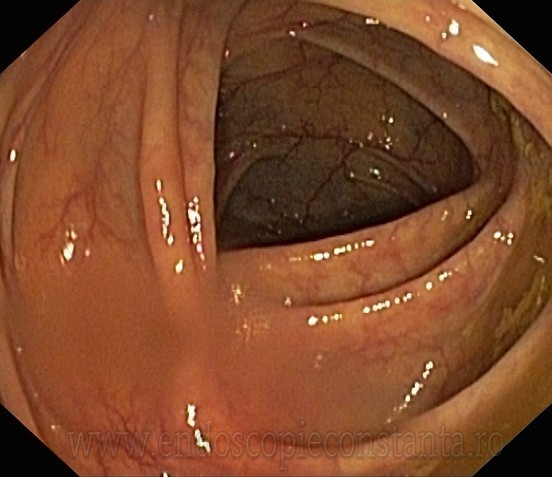

COLONOSCOPIE

Colonoscopia permite examinarea directa a interiorului intestinului gros. Examinarea se face cu un aparat optic ( colonoscop ) , care se introduce in tractul digestiv inferior , fiind manevrat pentru a ajunge in portiunea cea mai proximala a intestinului gros (cec) , si uneori si in ultima portiune a intestinului subtire (ileon terminal ) , fiind apoi retras , efectuindu-se in acest timp o examinare atenta.